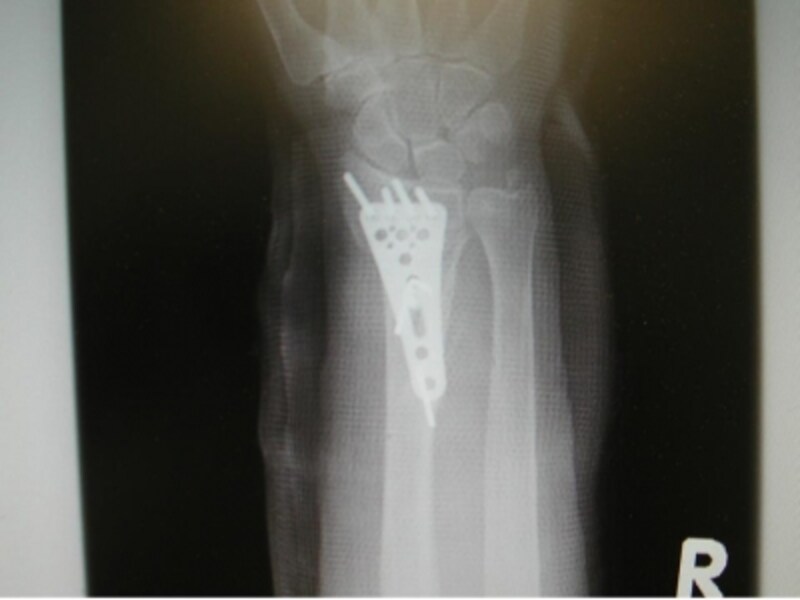

手術で橈骨を金属のプレートで固定しました。

側面像で骨片が良好な位置関係にあることがわかります。